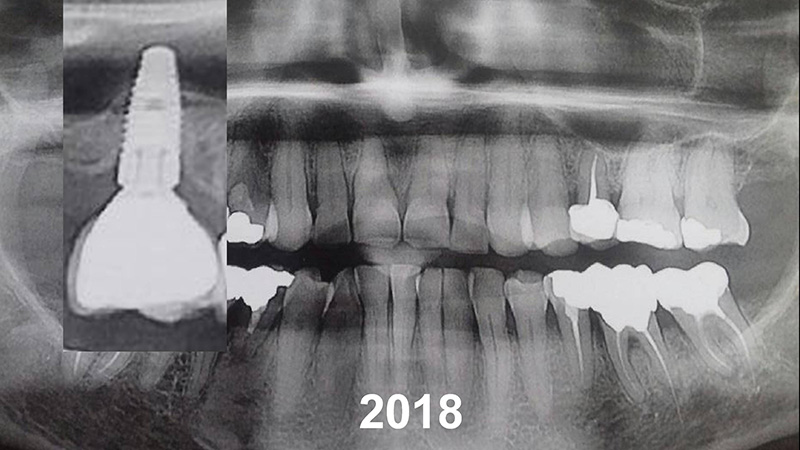

Pose d’un implant de 7 mm, puis évolution de l’os périmplantaire apicale au fil des années.

Patient se présentant pour le remplacement de la 26 et 27.

10 ans après, notez l’aspect radiologique de la corticale péri-implantaire.